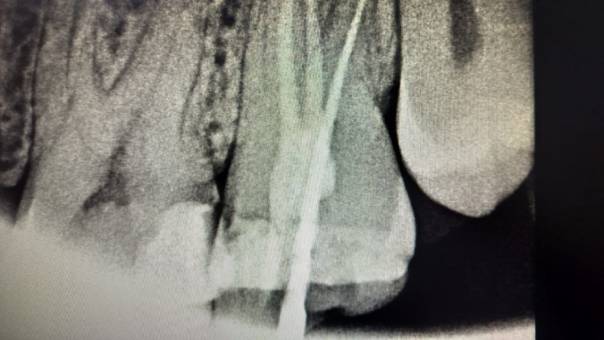

Our Treatment Approach:

After discussing the findings with the patient, we

recommended a Re-RCT, focusing on the missed distal

canal. This would allow us to eliminate the

infection and restore the tooth’s health.

Locating the distal canal